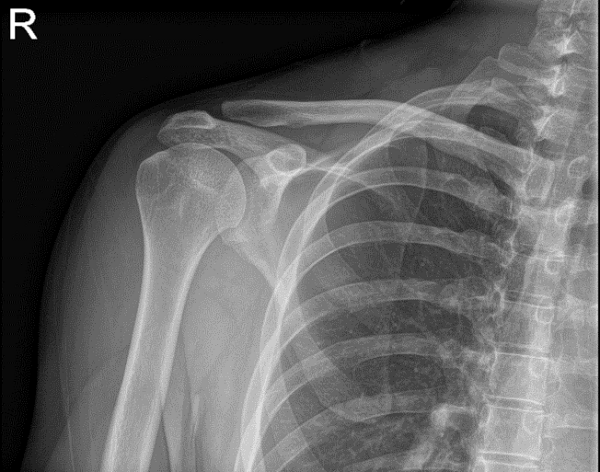

Bilateral Shoulder X-ray AP External and AP Internal

A 30-year-old patient visited our office with complaints of left collar bone pain. He was snowboarding, he was doing a jump and landed badly causing injury to his collarbone. He went to a hospital in CT where he was evaluated and x-rays were taken. He was discharged with a sling.

The severity of the pain was mild, when he was resting, when he was moving it. He denies any numbness or tingling. He presented results of x-ray which showed status post internal fixation with plate and screws of the left clavicle.